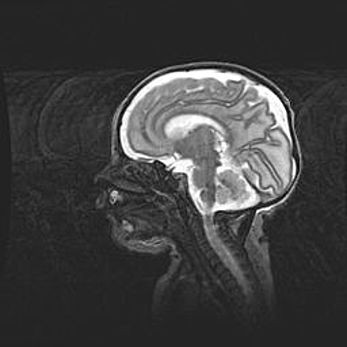

Церебральная ишемия II.

Возраст: 5 дней

Вес: 3400 г

Пол: женский

Окружность головы: 35 см

Срок гестации: 39 недель

Церебральная ишемия – это заболевание, характеризующееся недостаточностью (гипоксией) либо полным прекращением (аноксией) снабжения мозга кислородом по причине закупорки одного или нескольких сосудов. Это приводит к  что метаболическим расстройствам различной степени тяжести в тканях головного мозга, развитию коагуляционных некрозов и гибели нейронов.